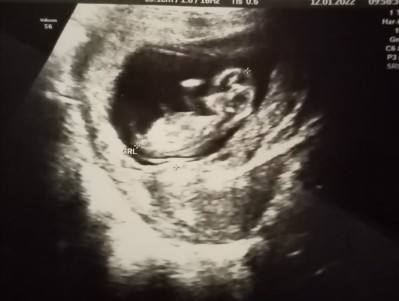

kızlar ben hamile kalmadan önce de sonrada rüyamda hep erkek bebek görüyodum hatta daha ortads bile yokken rüyamda erkek bebek gördüm demekki benim bebeğim böyle olucsk falam diyordum rüyamda simdi hamileyim erkek diye tahmin ediyorum sizce nedir

image

Paşa gibi kurulmuş sankim erkek:D

Kız bu bebek

Rüyanda erkek gorduysen kız oluyor :D bende erkek gördüm kızım oldu

Kiza benzettim Allah gönlüne göre versin bende rüyamda hep erkek gördüm kız oldu;))

Cnm bende hamile kalmadan ve kaldıktan snr hep kız gördüm rüyamda kız hissettim ama oğlum oldu. Herşeyin tersi olur derler :angel:

Hiç anlamam ultrason görüntüsünden Rabbim gönlüne göre versin canım. Benim rüyalarım hep tersi çıktı. Kızımda erkek bebek görüyordum oğlumda kız bebek :))